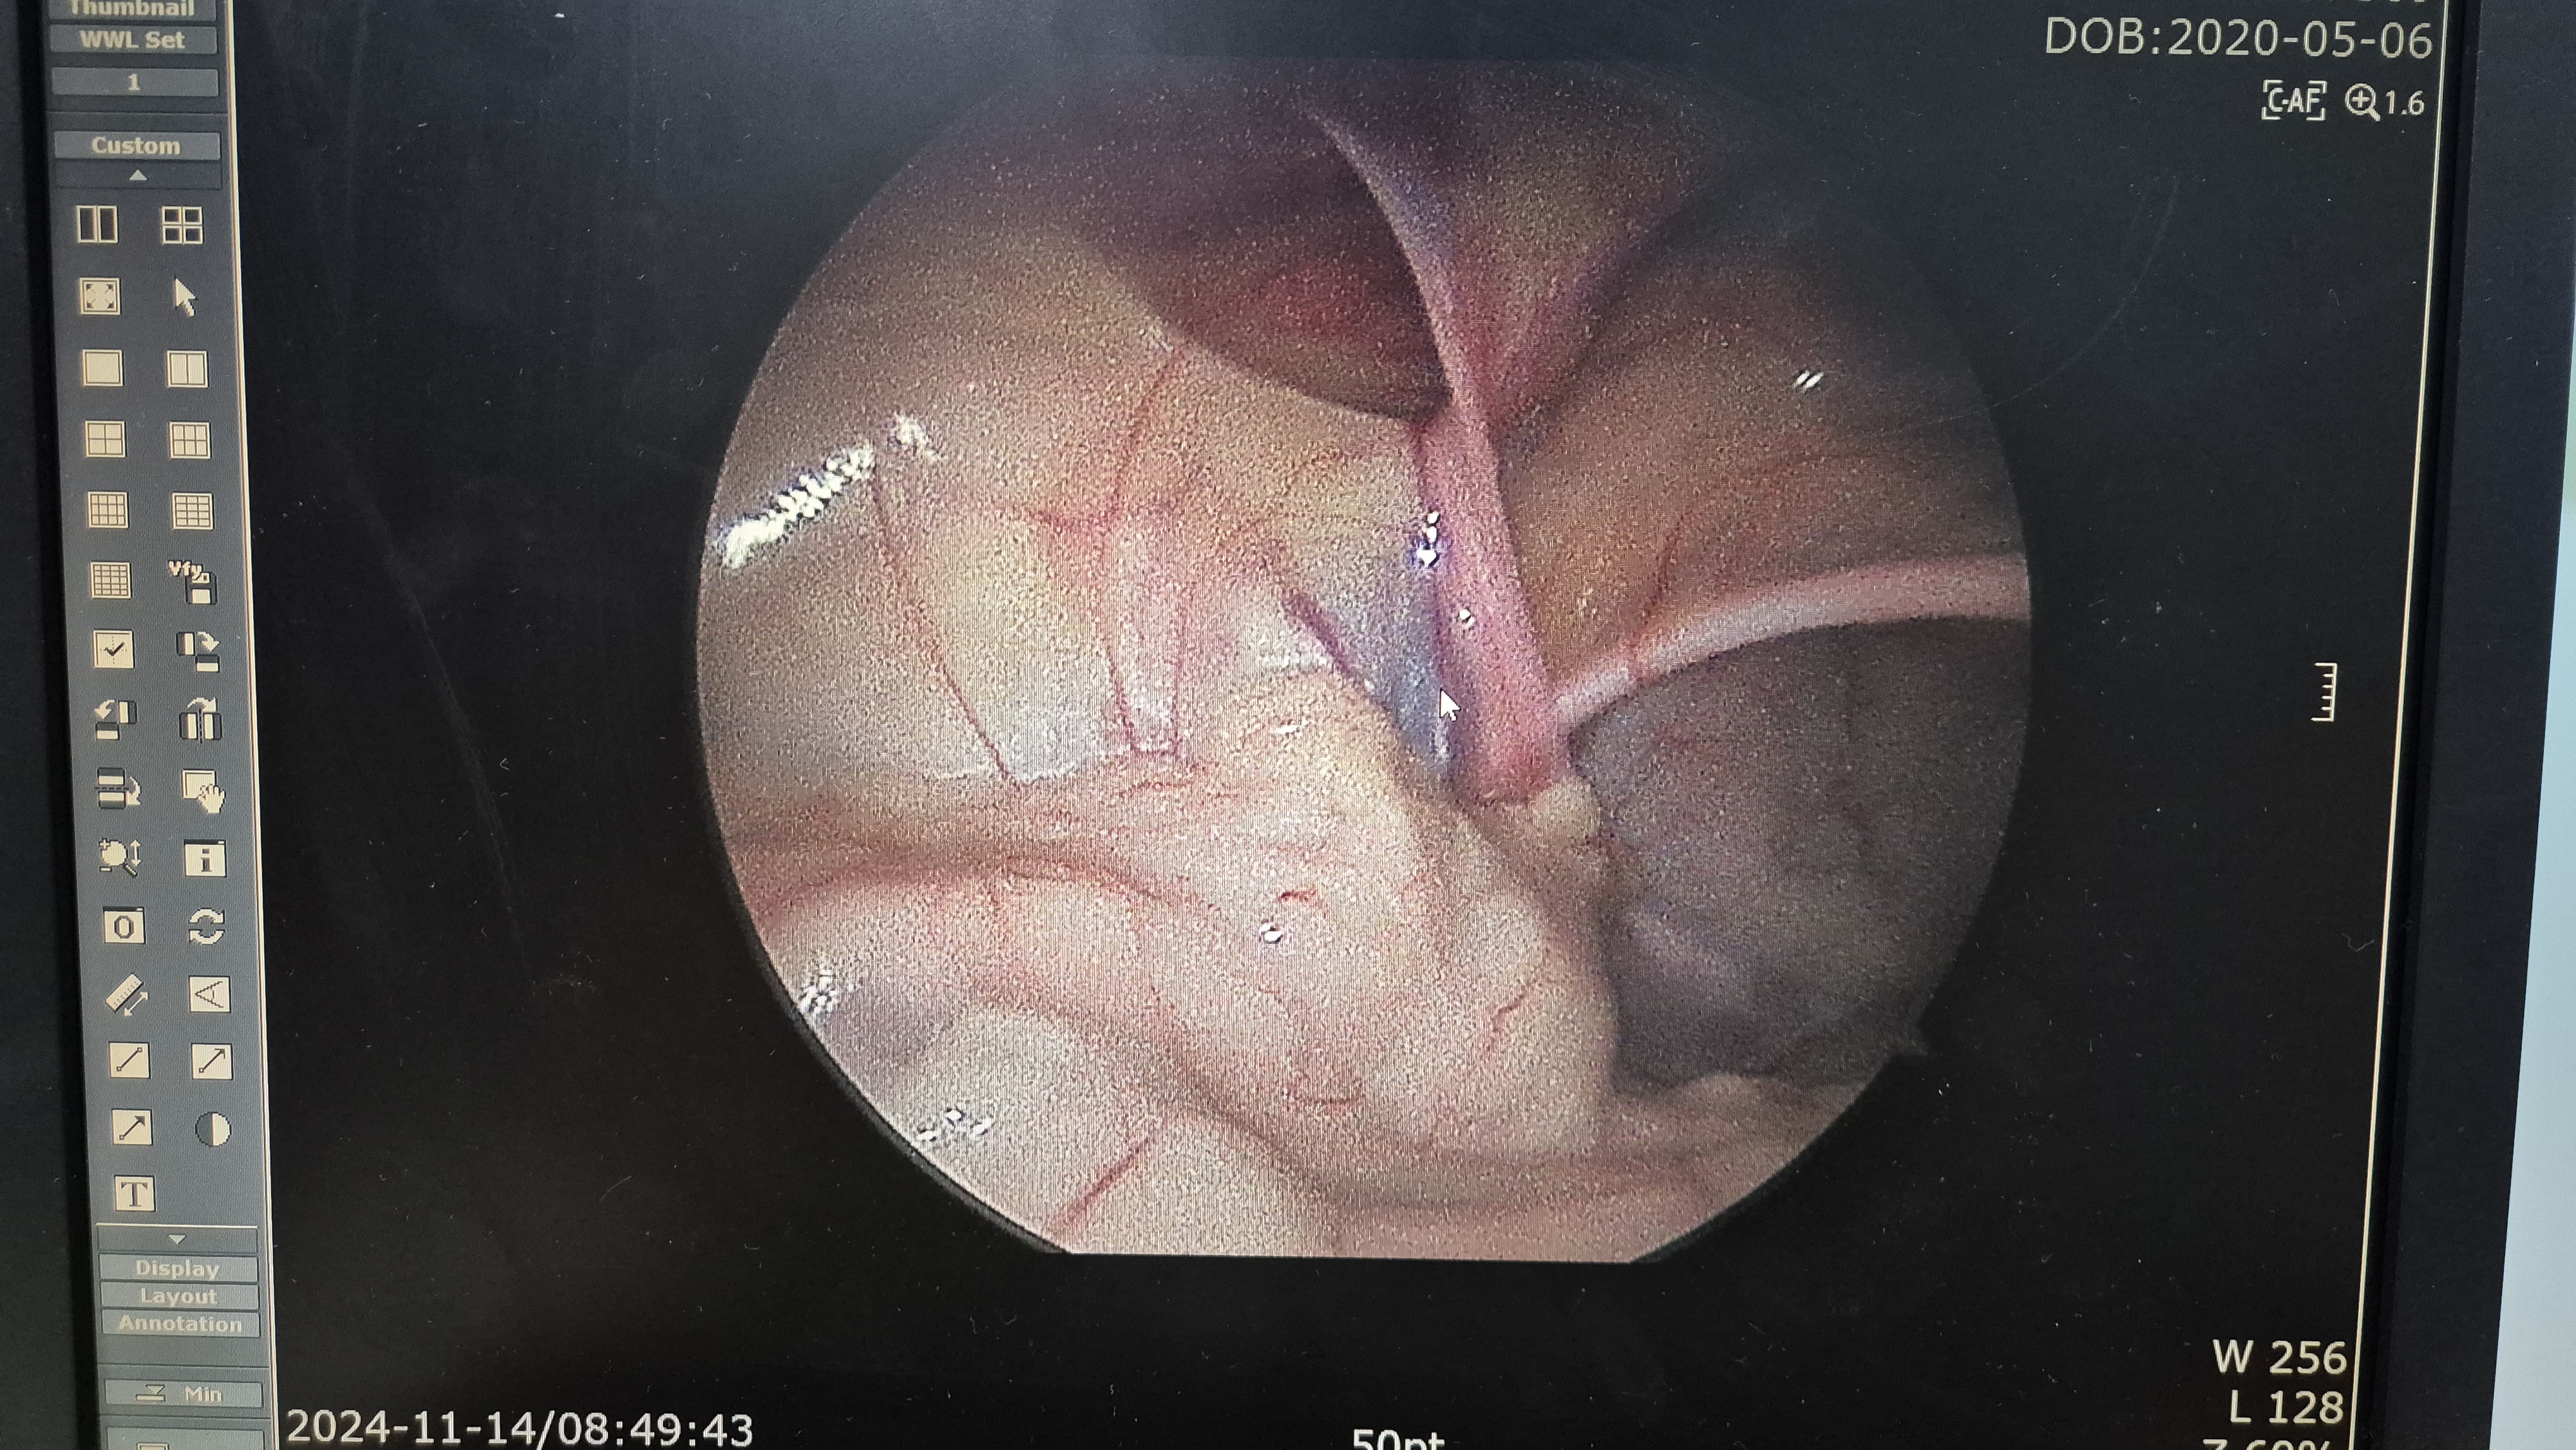

수술 들어가보니 양측에 모두 탈장이 있었고,

우측 서혜부 탈장.

교정중.

교정후.